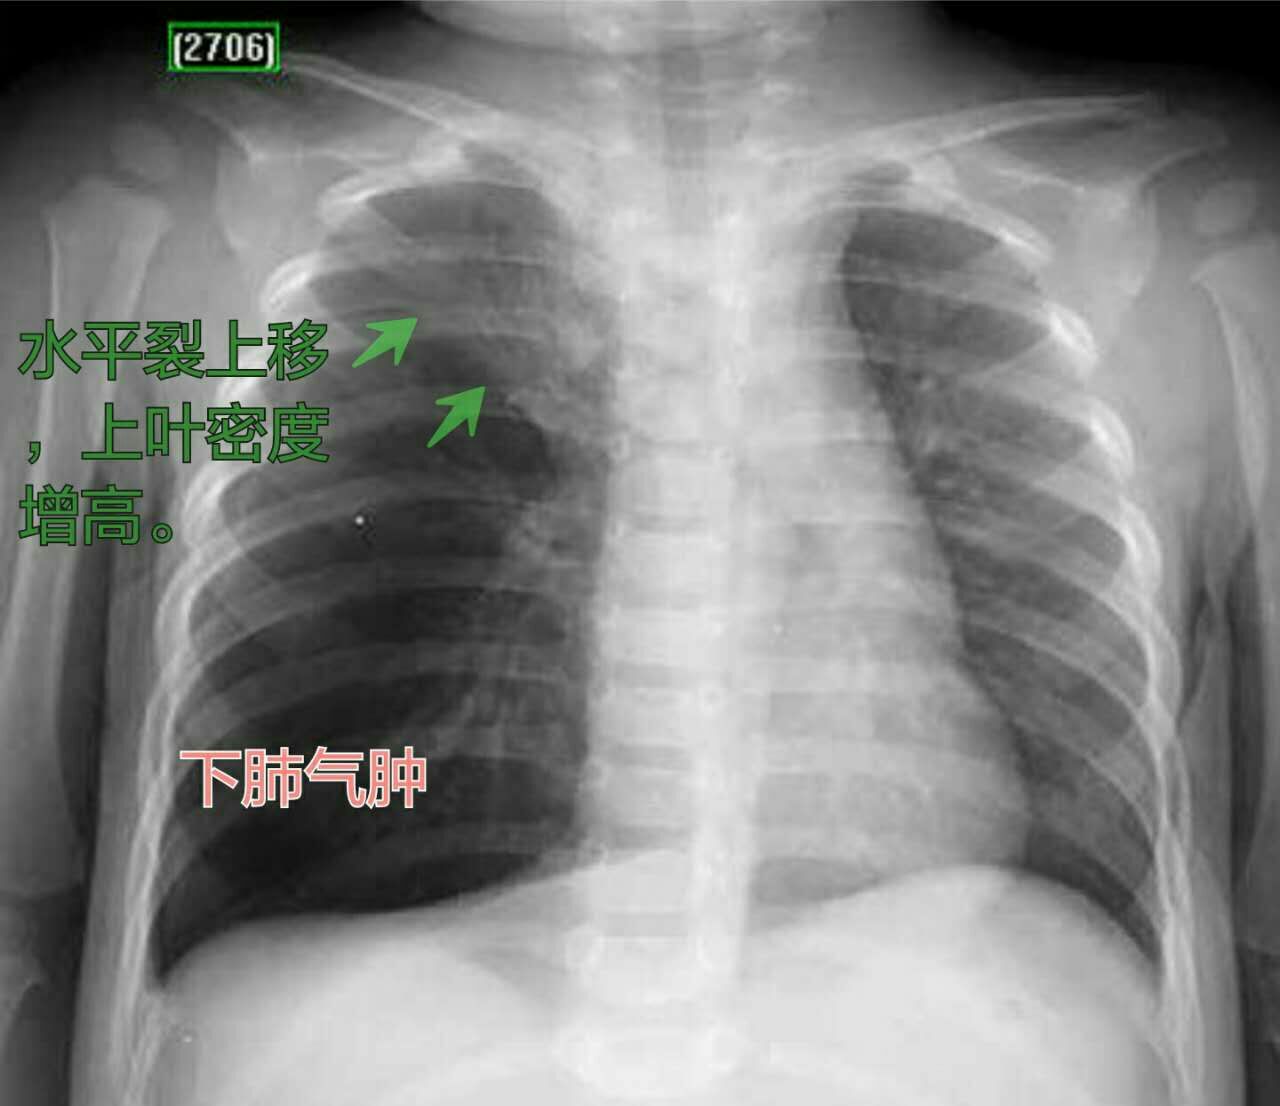

再看一例:

这是个1岁多的小男孩,反复咳嗽10多天,吃感冒药也没有效果,小儿科医生听诊双肺呼吸音不一致。

X光片显示右肺上叶体积缩小,右肺中下叶阻塞性肺气肿(更黑、体积更大),提示右侧气管异物,堵塞了右肺上叶支气管,同时不完全堵塞中下叶支气管形成活瓣样改变,气体进的多出的少,发生了中下肺叶的肺气肿。